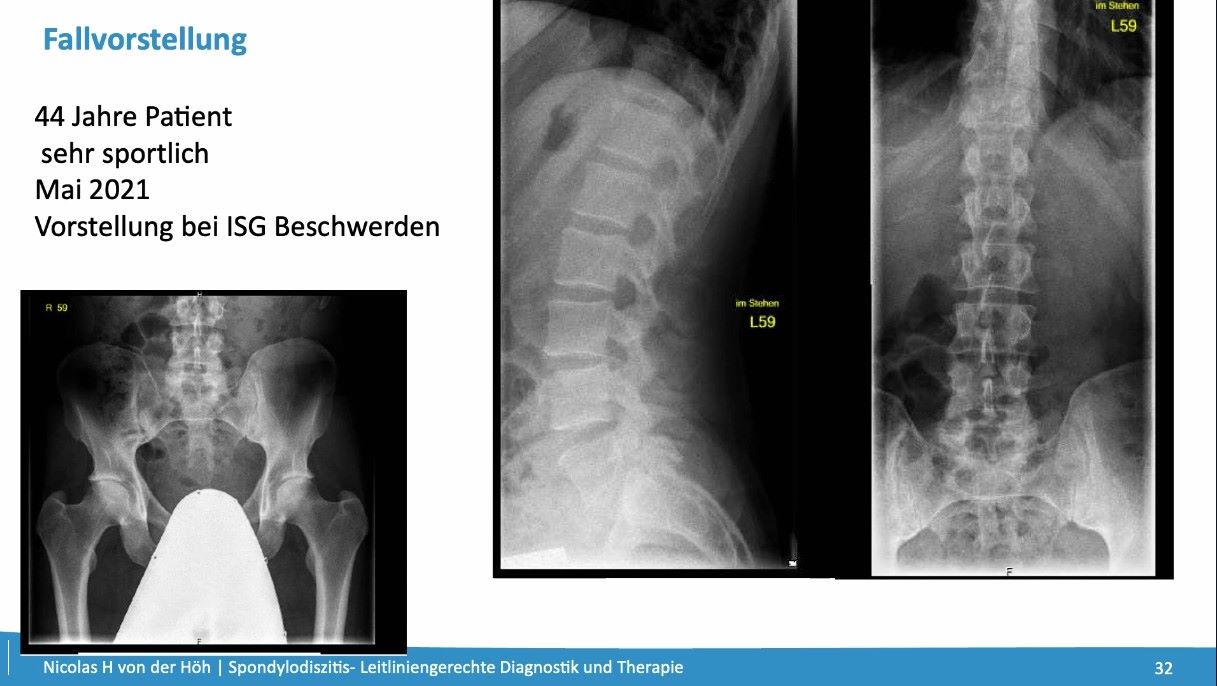

Leitlinie kompakt - #001: Spondylodiszitis

Leitliniengerechte Diagnostik und Therapie von Spondylodiszitis